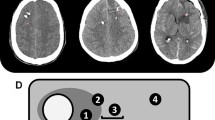

The first CT scan after surgery was obtained within 24 h after probe insertion to evaluate probe location. Probe location was assessed by an independent neuroradiologist and AL on all available head CT scans within the first 6 days. If the tip of the PbtO2-probe was located within a 1-cm distance of a focal hyperdense lesion (parenchymal hemorrhage) and/or focal hypodense lesion (perihematomal edema, focal brain edema, ischemia), the location was defined as perilesional, which mostly reflected the perihematomal area. If there was no focal lesion within 1 cm of the tip, probe location was graded as normal-appearing brain tissue. (Fig. 2) Whenever there was direct contact with the hemorrhage (intralesional location), the data was excluded from the analysis. Brain tissue hypoxia (BTH) was defined as mean PbtO2 < 20 mmHg over one hour as considered in the Consensus Conference on Multimodality Monitoring in Neurocritical care and the current Seattle Consensus Statement and was treated in a stepwise multifactorial approach using an institutional protocol including a CPP target > 70 mmHg [4, 13, 14].